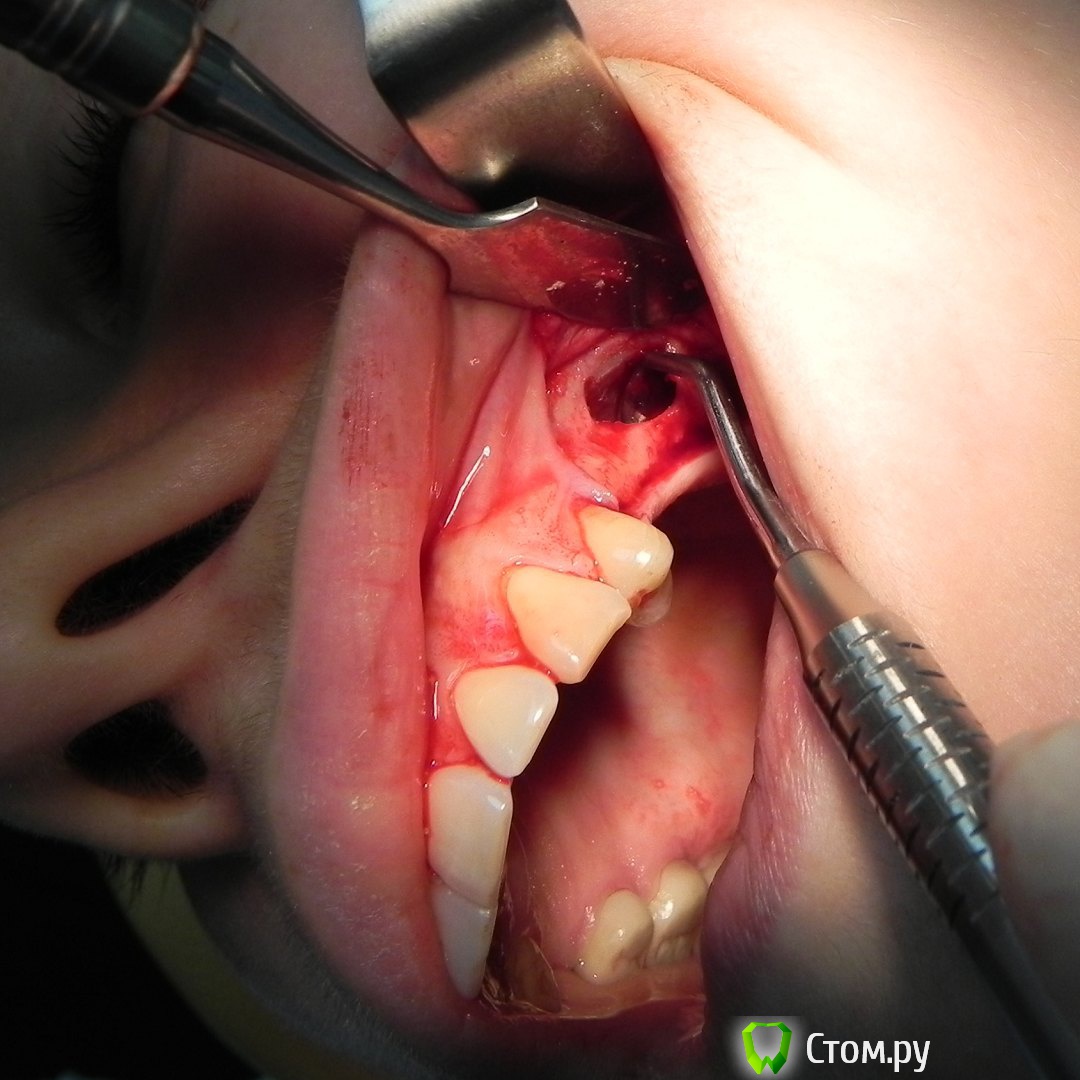

Kostoprav Опубликовано 12 июня, 2014 Автор Поделиться Опубликовано 12 июня, 2014 одновременно поставить -высоты кости не хватило ? 1-2 мм , я рисковать не захотел. 2 Ссылка на комментарий

rivezico Опубликовано 12 июня, 2014 Поделиться Опубликовано 12 июня, 2014 (изменено) одновременно поставить -высоты кости не хватило ? Изменено 12 июня, 2014 пользователем rivezico Ссылка на комментарий

Kostoprav Опубликовано 30 мая, 2015 Автор Поделиться Опубликовано 30 мая, 2015 все работает, чистая синтетика без ауто! это не единичный случай. 2 Ссылка на комментарий